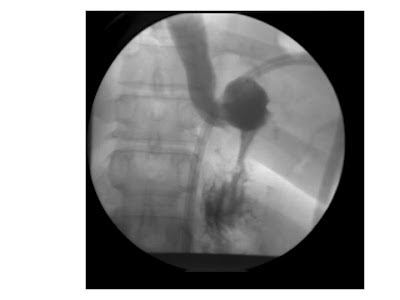

A gastric bypass is an effective procedure that achieves weight loss by both restrictive and malabsorptive mechanisms. The Roux-en-Y gastric bypass has become popular over the past decade as it results in substantial weight loss, but the long-term physiologic consequences are still being evaluated closely through multicenter research studies. It is an irreversible procedure. In this procedure, a portion of the small intestine (Roux-en-Y loop) is joined with a small portion of the upper stomach to create a small pouch (approximately 15 mL volume). The remainder of the stomach, duodenum, and proximal jejunum are excluded from food contact. In the standard procedure, the digestive secretions from the bile duct system and pancreas enter the jejunum 40- 50 cm from the stomach, resulting in malabsorption.

To promote greater weight loss, the procedure can be modified as a long limb gastric bypass (100 to 150 cm from the stomach) and is often considered in the superobese (BMI > 50). The procedure is well tolerated by most patients and is effective in achieving weight loss.[ix] Laparoscopic gastric bypass requires a high level of technical skill not possessed by most general surgeons.